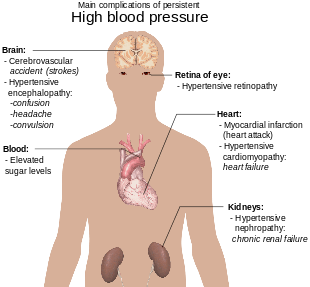

Hypertension

Hypertension is elevated blood pressure above "normal." Blood pressure is reported as fraction of systolic blood pressure over diastolic blood pressure and typically at the brachial artery while seated and measured in mmHg. The normal blood pressure changes with age with a general trend that it increases with age. Normal pressure for newborns is around 90/60 and young adults classically being 120/80 (pronounced "120 over 80").

Hypertension has significant impact on the cardiovascular system — other systems too — and is the motivating reason for treatment. Reduction of morbidity from hypertension is the end-goal of therapy.

- Complications of hypertension

- Hypertrophic cardiomyopathy

- Increased pressure results in hypertrophy of the myocardium, particularly left ventricular hypertrophy. Pulmonary hypertension — which is separate from "hypertension" described above — can result in right ventricular hypertrophy.

- Hypertensive crisis

- Generally considered to be a systolic blood pressure over 180. If there is no organ dysfunction it is called a hypertensive urgency, but if there is (e.g., confusion, breathlessness) then it is called hypertensive emergency.

- Hemorrhagic stroke

- Infarction of the brain due to internal bleeding from Charcot–Bouchard aneurysms.

- Hypertensive encephalopathy, hypertensive nephropathy, hypertensive retinopathy

- Damage to organs from chronic hypertension.